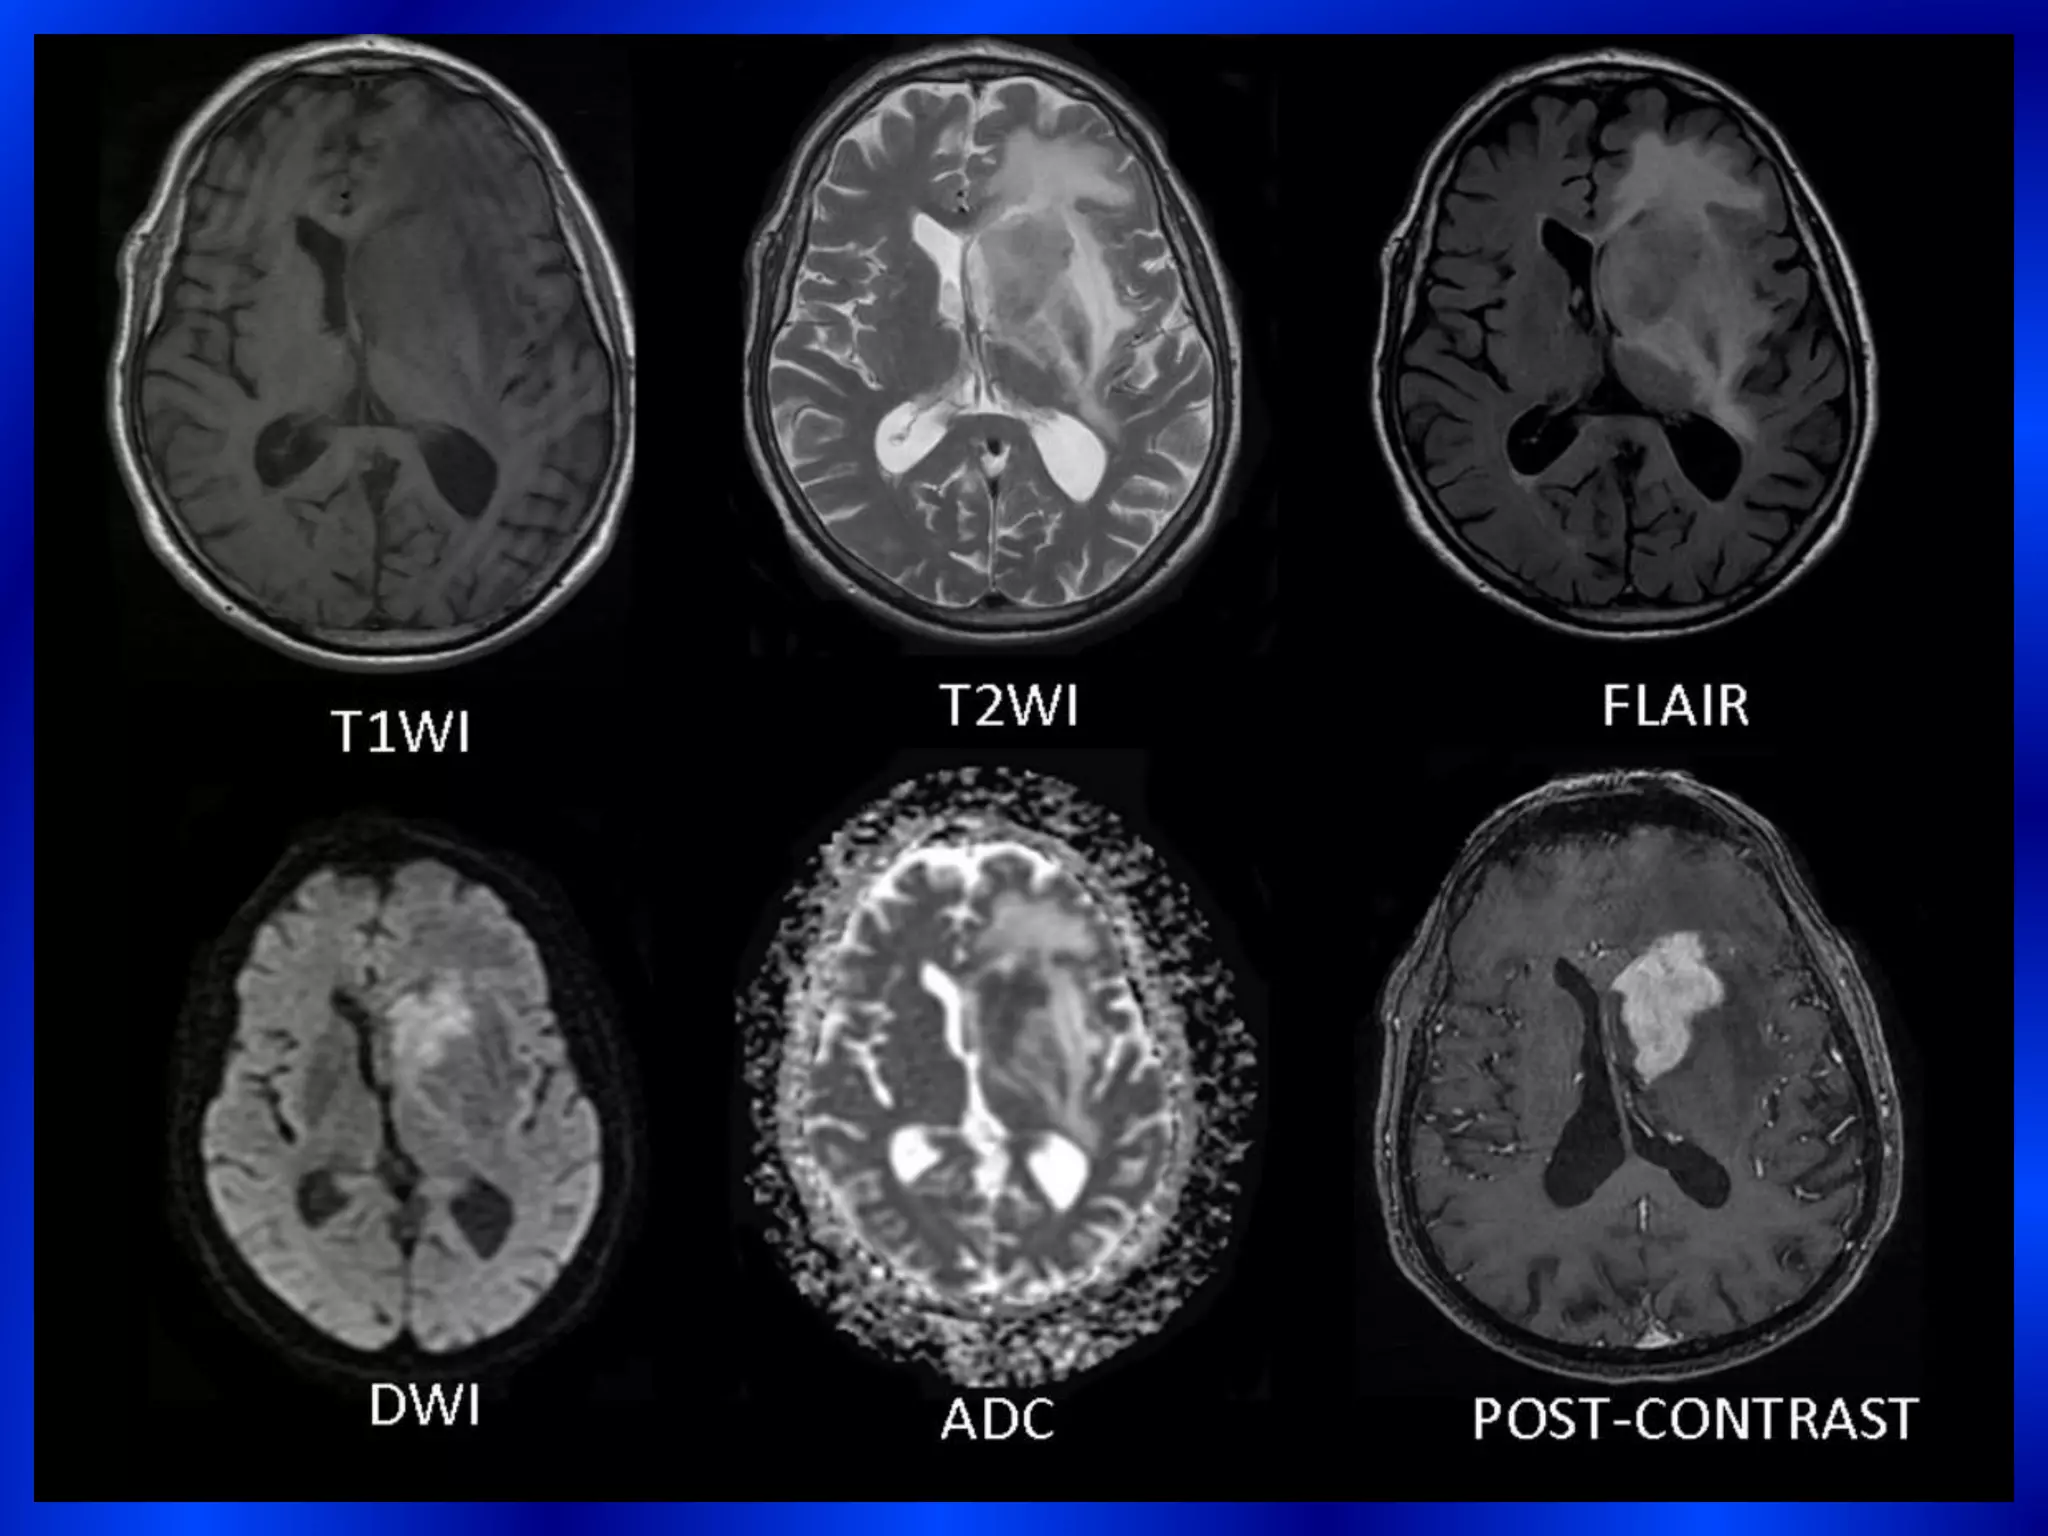

1)Usually solitary mass( 40-60%) hyperdense on CT with no

hemorrhage, necrosis or calcification.

2)Intermediate to low signal intensity on T1W images.

3)Isointense or hypointense signal relative to the gray matter on

T2W images.

4)Restricted Diffusion with intense homogeneous post-contrast

enhancement .

enhancement.